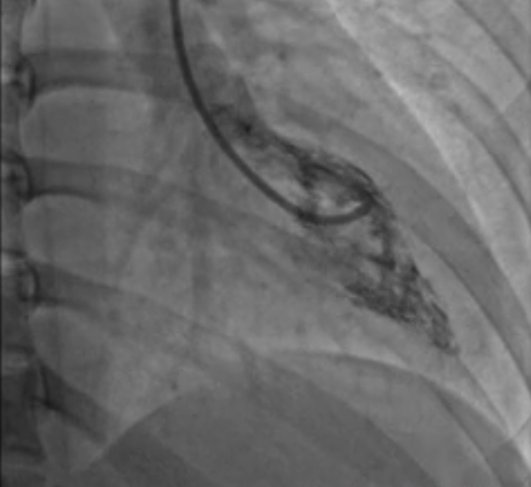

但由于患者体重为 240 多斤,心脏比正常人的都大一号,未能寻找到相匹配的心脏供体,因此心脏移植无法实施。在转入心血管内科后,病区主任、心肌病团队负责人辛辉教授迅速带领心肌病团队,针对患者病情积极查找「扩心病」的病因,考虑患者心衰的原因为「慢性炎症性心肌病」。

通过专家共同制定的个性化治疗方案,王先生的心功能明显改善,更避免了心脏移植手术,大大提高了生存质量。一个半月内,心脏射血分数由入院前的不到 30%,成功改善为 46%。

患者的成功救治,充分体现了复杂疑难心肌病团队的快速反应能力和专业素养。像王先生这样的案例还有许多,日常工作中,辛辉教授带领复杂疑难心肌病团队像侦探一般,分析查找患者的病因,使无数心肌病患者在精心治疗下,重获「心」生。目前,心肌病团队已成功开展心肌活检和基因筛查,为广大患者带来「心」的希望。